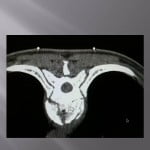

Numerous publications show the efficacy of this procedure (amoretti, huet) and the small rate of complication. In our experience, the coupling of scopy and scanner is fundamental. The axial cuts allow for visualization of the extremities.

The progression of trocars is done successively by controlling the scanners and lateral scopies. We use 13 gauges trocars, the penetration is performed manually, we avoid using a surgical hammer to limit he risks of displacements of bone fragments. We **transfixions the fractured centre with the two trocars bilaterally and symmetrically. , their ends being located medially to limit lateral leaks.

The cement is injected at the level of the anterior fragment of the fracture at its paste phase, then the trocars are slowly withdrawn at the level of the fracture while injecting progressively the cement and create a cement bridge with the anterior fragment and the fracture trait. A scanner control verifies that the end of the trocars is located perfectly in the fracture. The cement is injected slowly in the cannula and pushes with the needle of the trocar.

The lateral scopy controls real time diffusion of the cement in the fracture. The axial scannographic cuts confirm the correct diffusion in the fracture and the absence of para-vertebral leaks. The trocars are progressively withdrawn while injecting cement in the cannula with a needle. Standing up is authorized the day after with wearing corset. The clinical and radiological follow up is rigorous to avoid detecting all neurological sign of compression and appreciate the vertebral consolidation.